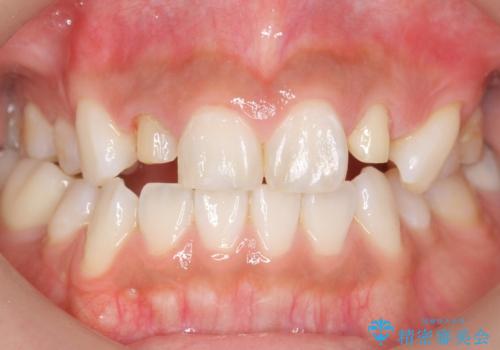

矯正せずに早く治したいという強いご希望により、セラミッククラウンによる補綴治療(上顎両側2の2本)を行いました。

天然歯のような自然な仕上がりに大変喜んで頂けました。

クラウンの種類:オールセラミッククラウン スペシャル